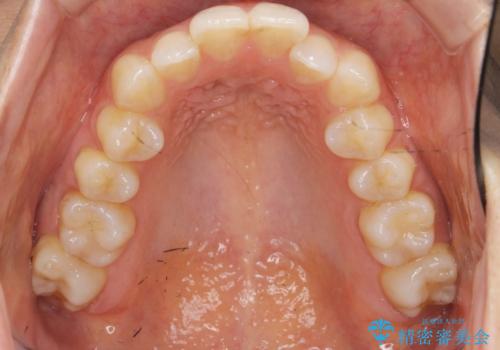

前歯のがたつきをしっかり治すマウスピース矯正

- 前歯のガタガタをきれいに並べたい、と希望され来院されました。

マウスピース矯正インビザラインのクリンチェックを用いて治療前にしっかりと歯並びのゴールのシミュレーションを行い、治療を開始します。

がたつきのないきれいな歯並びに仕上げることができ、満足いただくことができました。